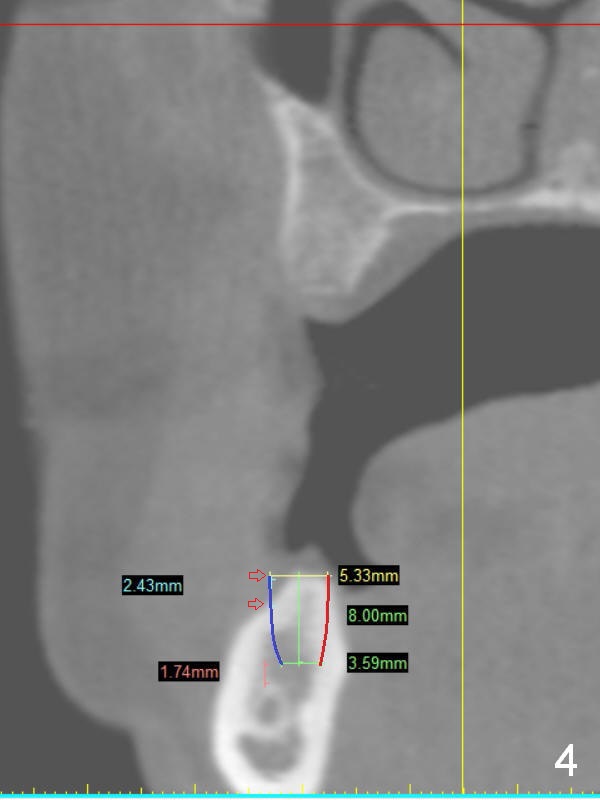

A 49-year-old lady is petit. An implant is placed at #3 and ready for restoration. The crest at #30 is narrow (Fig.1 ^). Bone density at the cortex, around the Inferior Alveolar Canal (IAC) and the medulla is D1, D2 and D3, respectively. It appears that a 10 mm bone-level implant is too close to IAC (Fig.2), whereas a 8 mm one has enough clearance (Fig.3,4). With the same diameter, there will be less thread exposure if the implant is placed a little lingually (Fig.4 (between arrows), as compared to Fig.3).

Since the patient is small and the cortex is dense, a 4.5x8.5 mm UF implant should meet masticatory force as long as #14 and 19 also receive implants. Her mouth should be small. Consider using sensor 1.舌侧骨板厚,适当磨去,让植体舌侧移动。